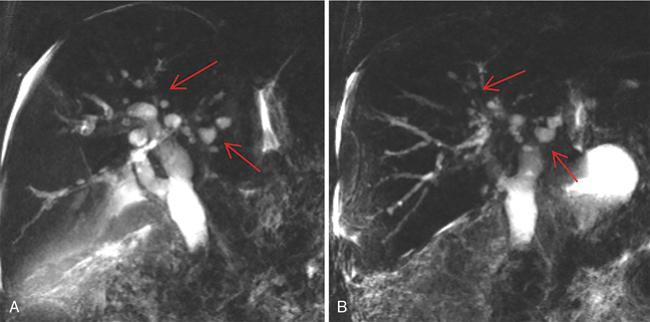

Ritu K. Kashikar, Shrinivas B. Desai, Chandresh Karnavat, Nilesh Doctor The biliary tract is subject to a variety of abnormalities. The spectrum includes benign diseases of autoimmune, infective, ischaemic, infiltrative aetiologies and malignant disorder, which most importantly represents cholangiocarcinoma. Imaging in particular magnetic resonance cholangiopancreatography (MRCP) plays a vital role in diagnosis and follow-up of these disorders. Multidetector computed tomography (MDCT) and magnetic resonance imaging (MRI) are also crucial in preoperative staging of biliary malignancies and making decisions regarding resectability and extent of resection. This chapter focuses on important benign and malignant disorders of the biliary tree and imaging features that aid in differentiation of various entities. A variety of disorders affect the biliary tree. Most biliary disorders manifest as biliary dilatation. The various causes are listed in Table 9.15.1. Imaging plays an important role in identification of aetiology based on pattern of involvement in association with clinical picture. USG is often the first investigation in a patient with jaundice. USG is excellent at showing biliary dilatation. It may be useless in assessing level of obstruction and biliary stones. Changes in liver morphology, development of cirrhosis is accurately done on USG. Early changes in conditions like primary sclerosing cholangitis (PSC), presence of intrahepatic ductal strictures, thickening of common bile duct (CBD) are, however, not confidently seen and need imaging modalities like MRCP and computed tomography (CT). Staging of hilar cancers is also best done on CT or MRI with contrast. Contrast-enhanced CT is extremely accurate in staging hilar cancers. It is a preferred modality to access radial spread of the disease and vascular involvement. Subtle changes of PSC and autoimmune cholangitis may however be missed and MRCP is preferred in these conditions. The protocol for evaluating biliary disease is standard plain scan followed by early, late arterial, portal venous and parenchymal phases similar to that obtained for focal liver lesions. Delayed phase images should be obtained for hilar malignancies, which often show delayed enhancement. MRCP with or without contrast is the modality of choice in diagnosing and characterizing biliary diseases. Owing to its noninvasive nature, it has replaced endoscopic retrograde cholangiopancreatography (ERCP) in the initial evaluation and follow-up of a variety of biliary pathologies. Absence of radiation exposure makes it suitable to obtain follow-ups in patients requiring serial scanning. The ability to diagnose abnormalities of both intra- and extrahepatic biliary tree, level of obstruction, longitudinal and radial spread of neoplastic process make it an ideal modality. MRCP protocol includes T2 weighted single-shot fast spin-echo, T1 weighted in phase and opposed phase gradient echo, diffusion-weighted imaging, T2-weighted fat-suppressed fast spin-echo in axial and coronal. A pre contrast three-dimensional T1-weighted fat-suppressed spoiled gradient-echo image is obtained in addition to 3-D MRCP. Postcontrast protocol includes dynamic three-dimensional T1-weighted fat-suppressed spoiled gradient-echo (in arterial, late arterial and portal venous, parenchymal and delayed phases). Since the advent and widespread use of MRCP, the utility of ERCP in diagnosing biliary pathologies has significantly reduced. ERCP is primarily used when stenting or other procedures need to be performed in the same setting. Although an invasive procedure with postprocedural risk of pancreatitis ERCP allows excellent depiction of biliary changes in conditions like PSC, recurrent pyogenic cholangitis (RPC) and IgG4-related disorders. Endoscopic USG (EUS) is an excellent modality in diagnosing lower bile duct pathologies and also has the added advantage of obtaining a biopsy in the same setting. EUS is less invasive than ERCP and overall safer. PSC is a premalignant cholestatic liver disorder characterized by bile duct strictures secondary to bile duct inflammation and fibrosis. Cirrhosis of liver can develop secondary to this condition and patients are at a high risk for biliary and colonic cancers. PSC is a relatively rare disease, with an incidence of less than 50 per 100,000 patients though it varies in various location. It is diagnosed in young patients aged 30–40 years and is twice as common in men than in women. Similar to other autoimmune diseases, genetic susceptibility is likely to be instrumental in the development of PSC after exposure to a trigger. There is also a strong association between PSC and human leukocyte antigens (HLAs). Environmental factors such as childhood microbial exposure also play an important role in disease pathogenesis. A strong association of PSC with inflammatory bowel disease (IBD) is seen. There is a 100-fold increased risk of developing PSC among siblings. PSC can be asymptomatic but may present with cholestatic symptoms such as jaundice, pruritus, fatigue and right upper quadrant pain, steatorrhoea and episodes of acute bacterial cholangitis. There is marked elevation of alkaline phosphatase (ALP). A twofold to threefold increase in serum alanine and aspartate aminotransferase (AST) can be seen. Elevated bilirubin is usually seen in advanced disease, malignancy or those with choledocholithiasis. Various serum antibodies can also be elevated in PSC. These have been enlisted in Table 9.15.2. On liver biopsy, classic pathologic features of periductal concentric fibrosis or ‘onion skin’, around the affected ducts can be seen. This is however not a pathognomonic finding and is seen in less than 40% of biopsy specimens. Therefore, biopsy is not routinely used as a diagnostic tool for PSC and is reserved primarily for disease staging. MRI with MRCP best depicts the biliary changes in PSC and is the modality of choice. While CT and USG may show biliary dilatation and changes of cirrhosis in advanced cases, they fail to show early changes (Table 9.15.3). USG is an effective modality for the visualization of dilatation and diffuse wall thickening of the extrahepatic bile duct. Other feature seen on USG is bright echogenic portal triad. However, the role of USG in the diagnosis of early PSC is limited owing to suboptimal assessment of the intrahepatic biliary ducts. Features of advanced disease such as heterogeneous coarse echogenicity can be readily detected with USG. The major benefit of performing US is to guide liver biopsy. Also, liver stiffness as assessed by transient elastography correlated well with the degree of liver fibrosis in PSC patients. CT can demonstrate some findings suggestive of sclerosing cholangitis such as focal, discontinuous, often peripheral intrahepatic biliary duct dilatation and thickening with enhancement of the bile ducts owing to inflammation. CT is effective in helping exclude other causes that can result in biliary stasis and dilatation such as hepatic and pancreatic lesions. CT is also excellent in diagnosing tumours, which may sometimes have similar presentation. Concomitant changes of IBD, if present, can be seen. However, CT is limited in assessment of biliary strictures and visualization of disease involving small peripheral bile duct, especially in the early stages of the disease. CT shows changes of cirrhosis in liver and assessing changes of portal hypertension. MRCP is diagnostic imaging modality of choice in the workup of patients with suspected PSC, as recommended by both the AASLD and EASL guidelines. MRCP has high diagnostic sensitivity (86%) and specificity (94%) for the detection of PSC (Table 9.15.3). Multifocal short segmental strictures in the intra- or extrahepatic biliary tree with intervening normal or dilated duct leading to beaded appearance are seen in early disease. The location in strictures is usually at the biliary bifurcation and are disproportionate to upstream dilatation. Advanced cases show pruning of peripheral biliary radicals secondary to advancing fibrosis obliterating the smaller ducts. An obtuse angle between the central and peripheral ducts is suggestive of PSC. Diverticula and webs also can be seen, though not pathognomonic (Table 9.15.4) (Figs. 9.15.1–9.15.3). Strictures of the CBD of less than 1.5 mm and of left, right or common hepatic duct (CHD) of less than 1 mm are defined as dominant stricture. A dominant stricture is associated with worse prognosis in part due to development of cholangiocarcinoma. MRCP plays an important role in raising the suspicion and guiding treatment. A dominant stricture may be confused with hilar cholangiocarcinoma on imaging and it is often impossible to distinguish the two based on imaging alone (Table 9.15.4) (Fig. 9.15.4). Changes in liver morphology are seen in the form of distortion. The classical change described in PSC includes hypertrophy of the caudate lobe and atrophy of the left lateral and right posterior segments of the liver. Hypertrophy of caudate lobe is more frequent in PSC than cirrhosis from other aetiologies. Other parenchymal changes include heterogeneity of liver, periportal cuffing, peripheral inflammation, cirrhosis and features of portal hypertension. Hyperintensity of the liver parenchyma in PSC on nonenhanced T1-weighted images has been reported. Wedge-shaped peripheral atrophic areas of confluent hepatic fibrosis are seen as high T2-weighted signal intensity. Periportal oedema is visualized as high signal intensity in periportal region on T2-weighted. Increased heterogeneous peripheral enhancement of the liver parenchyma can be seen and is likely due to the altered blood supply in those areas in response to parenchymal inflammation (Table 9.15.4) (Figs. 9.15.5 and 9.15.6). MR elastography is the most accurate noninvasive method for the diagnosis and staging of liver fibrosis and could potentially replace liver biopsy. It is predictive of progression to decompensated liver disease. However, lack of wide availability are still major limiting factors. MR elastography is not influenced by obesity or anatomical conditions (e.g. narrow intercostal spaces and ascites) and the sample size of the liver is significantly higher and hence has several advantages over ultrasound elastography (Table 9.15.5). Besides these features, enlarged reactive abdominal lymph nodes, commonly periportal and portocaval lymph nodes, are commonly diagnosed in PSC and should not be misdiagnosed as a lymphoproliferative disorder or metastatic disease. Though ERCP has higher diagnostic accuracy in detecting PSC, its role is limited to intervention required in PSC due to its invasive nature and potential complications. Also it is recommended that MRCP be performed prior to ERCP as a preprocedural MRCP can provide a road map to the endoscopist. Small duct PSC is a variant PSC syndrome with biochemical markers and histologic features suggestive of PSC with normal cholangiography. It is associated with better prognosis. Approximately one-fourth of patients’ progress to classic PSC in an average of 8 years. Bile duct calculi are a common complication of PSC. Pigmented bile duct stones are common owing to biliary stasis. Both intrahepatic and extrahepatic biliary stones can be found. However, the presence of biliary tree stones is not an essential diagnostic feature. Soft calcific foci within dilated bile ducts can be seen on US and CT images. MRI with MRCP is the imaging modality of choice to detect bile duct stones and appear as focal areas of signal-intensity-void filling defects on T2-weighted images. Usually isointense at T1-weighted imaging but frequently are hyperintense. The presence of biliary strictures puts these patients at risk of bacterial cholangitis in PSC patients. The classic Charcot triad of fever, abdominal pain and jaundice can be seen. Early enhancement of the biliary wall due to the biliary duct inflammation is a common finding with peribiliary reactive hepatic parenchymal changes. Cholangitic abscesses may sometimes be seen. PSC patients are at high risk of developing cholangiocarcinoma during the disease course with and a total risk of 10%–15%. Approximately 30% of all cholangiocarcinomas are detected within the first year of establishing a diagnosis of PSC and so it is important to be suspicious even at the time of PSC diagnosis and to survey for early detection. Rapid clinical deterioration, worsening of jaundice, pruritus, weight loss along with elevation in serum bilirubin and ALP should raise suspicion of PSC. It may be difficult to distinguish benign from malignant strictures. Progressive bile duct wall thickening, irregularity, enhancement, new onset biliary dilatation, dominant stricture or development of focal strictures with dilatation and ipsilateral atrophy are indeterminate features that may raise possibility if occult cholangiocarcinomas. Perivascular thickening, vascular involvement or occlusion are features favouring malignancy. Definite diagnosis is however often not possible on imaging alone and a brush biopsy should be taken in patients with new onset clinical symptoms, elevated tumour makers or above-mentioned indeterminate imaging features (Table 9.15.7). The most common subtype of cholangiocarcinoma in PSC patients is periductal type, characterized by long segment irregular wall thickening along the bile duct with no identifiable mass. The lesion is hypointense on T1W1 images and hyperintense on T2W1 images showing progressive enhancement on contrast study. The tumour could be at the bifurcation and can cause abrupt cut-off, commonly presenting as Klatskin tumour (Fig. 9.15.7). Combined UC and PSC is associated with a higher risk for colorectal carcinoma than UC alone. PSC is considered as an independent risk factor for development of colorectal carcinoma in patients with UC. Malignancy tends to involve the right colon or more proximal parts of the colon. Clinical presentation and history in patients with ascending cholangitis differ from those with PSC. Fever, pain and jaundice dominate the presentation in patients with ascending cholangitis while patients with PSC may be asymptomatic. The typical findings of PSC including biliary duct stenosis, beading or pruning are not typical findings in the newly diagnosed cases of acute ascending cholangitis. Wedge-shaped peripheral and/or intrahepatic peribiliary foci of increased T2 signal around the dilated radicals with arterial and/or delayed parenchymal enhancement has been described in ascending cholangitis. Patients with RPC present with recurrent episodes of abdominal pain, fever, jaundice and chills. These features differ from those in patients with PSC. Hepatolithiasis with pigmented stones in the biliary tree and upstream and downstream duct dilatation are typical imaging features in RPC (Table 9.15.8). Ischaemic cholangiopathy is a form of biliary injury resulting from decreased arterial supply. History of liver transplantation is the key in diagnosing ischaemic cholangiopathy. Biliary strictures in AIDS cholangiopathy are indistinguishable from PSC. However, the combination of papillary stenosis and intrahepatic ductal strictures appears relatively unique to AIDS cholangiopathy; this combination is not found in PSC. Clinical history may help to distinguish one from the other. Effective medical therapy for PSC is lacking. Oral ursodiol (ursodeoxycholic acid) is one of the main treatment options of cholestatic diseases though does not prevent disease progression. Azathioprine and steroids are recommended for use in patients with AIH as well as those with AIH–PSC overlap syndrome. Vedolizumab is a gut-specific monoclonal antibody that has been tried but the clinical utility in PSC–IBD patients remains under investigation. Dilatation of biliary strictures, stenting, lithotripsy and stone extraction can be done with the aid of ERCP and percutaneous transhepatic cholangiography (PTC). The only definitive cure of PSC is, however, liver transplantation. Treatment of complications like choledocholithiasis stone removal can be accomplished by using standard endoscopic techniques with or without sphincterotomy, with balloon or basket extraction for extrahepatic biliary stones. For bacterial cholangitis, immediate administration of broad-spectrum antibiotic therapy is recommended and in abscess formation percutaneous drainage with intravenous antibiotic therapy shows favourable outcome compared with surgical drainage. Incidence is 20%–25%. Diagnosis of recurrent PSC requires careful evaluation, as there are other causes of biliary changes after liver transplant with similar features. Nonanastomotic biliary strictures imply the diagnosis of recurrent PSC only if they occur more than 90 days after transplant. Characteristic multifocal strictures and segmental dilatations of biliary ducts are suggestive findings. MRCP is the initial modality. RPC is characterized by a triad of recurrent biliary sepsis, inflammatory biliary strictures and intrahepatic stones. Fifty per cent of patients may have acute pancreatitis. Oriental cholangiohepatitis, primary hepatolithiasis, Hong Kong disease and oriental infestational cholangitis. Prevalence in the third and fourth decades of life with equal frequency among men and women peak. Southeast Asia predominantly in rural population and in lower socioeconomic groups. Gut-derived organisms lead to sepsis, which initiates a cascade of events, which leads to a chronic, progressive and recurrent inflammatory process in cholangioles. Associations with Clonorchis sinensis, Opisthorchis species, Fasciola hepatica and Ascaris lumbricoides infestations have been suggested. Common organisms cultured from bile include Escherichia coli, Klebsiella, Pseudomonas and Proteus species and anaerobes. Structural biliary abnormalities may develop before stones are demonstrable. Strictures may be seen at cholangiography without stones and vice versa. Entrapped stones cause stasis, sepsis, scarring and stricturing with the increasing lithogenicity (Table 9.15.9). Typically present with abdominal pain, fever and jaundice (the Charcot triad) and commonly provide history of repeated episodes. Routine investigations may demonstrate leukocytosis, deranged liver enzymes with obstructive pattern. Elevated cholestatic markers (bilirubin, ALP and gamma GT) and deranged LFTs can be seen. Serum inflammatory markers can be elevated. Additional tests aiding in differential diagnosis include autoantibodies, ANCA, CA19-9 and serologic tests for Echinococcus. Histology is usually not required. It shows fibrous mural thickening of bile ducts and periductal tissue, as well as acute and chronic inflammatory changes. The imaging features include changes in bile ducts, development of calculi and changes in the parenchyma. The disease affects intrahepatic ducts more than the CHD and CBD. Disproportional dilatation of central intrahepatic ducts and extrahepatic bile ducts is seen with nondilated or minimally dilated peripheral ducts, leading to abrupt tapering of bile ducts. All segments of biliary tree may be involved, but the lateral segment of the left lobe is most often and extensively involved most likely because left hepatic ducts come off at a more acute angle compared with the right hepatic ducts, thus predisposing to stasis and stricture formation (Table 9.15.10). Hepatolithiasis is common in patients with RPC. Stones are composed mainly of bile pigments with variable calcification. There may be single or multiple stones scattered in the intra- or extrahepatic ducts or both. The dilatation of the extrahepatic duct is generally not related to the location of the stone. Ducts both proximal and distal to the stone are dilated. Parenchymal atrophy most commonly involves the left lateral and right posterior segments while hypertrophy of the caudate and right lobe is seen. USG shows dilatation of the central intrahepatic and extrahepatic ducts, with relative sparing of the peripheral biliary tree. Hepatolithiasis can be seen in 90% of cases. The echogenicity and acoustic shadowing of calculi may vary depending on extent of calcification. There is often associated periportal echogenicity. Ultrasound may be useful in performing image-guided percutaneous drainage of abscesses or biopsy of suspicious lesions. Limitations include inability to detect subtle intrahepatic ductal dilatation and heavy stone burden obscuring evaluation of underlying hepatic parenchyma. Contrast-enhanced CT is increasingly being used as first line of imaging. It allows for detection of characteristic disproportionate dilatation of the extrahepatic and central intrahepatic ducts. Contrast-enhanced CT also allows for detection of bile duct wall enhancement, suggestive of acute cholangitis. Ninety per cent stones are hyperdense to liver parenchyma on nonenhanced scan. Extent of calcification in calculi may vary. Parenchymal atrophy affects left lateral segment most frequently, followed by right posterior segments. Eventually, changes of cirrhosis can be seen. Heterogeneous appearance of liver parenchyma with segmental steatosis and altered enhancement can be seen particularly during acute attack. Pneumobilia is not infrequent and can usually be attributed to recent procedures or surgeries like bilioenteric anastomosis. It may, however, be seen in patients without history of prior interventions due to recent passage of stone through the ampulla or less commonly cholangitis related to gas forming organisms (Fig. 9.15.8). Subtle intrahepatic ductal strictures and noncalcified stones may be missed on CT. MRCP allows visualization of both intra- and extraductal disease and can reveal complete extent, severity and complications of the disease. Even noncalcified calculi which may be missed on CT or sonography, are seen as intraductal filling defects on heavily T2-weighted images and may appear hyperintense to the liver on T1-weighted images. MRI demonstrates central and extrahepatic duct dilatation with decreased arborization and abrupt tapering of peripheral ducts. MRI particularly MRCP sequences accurately depicts stenotic segments and delineates the entire biliary tree, including the proximal part of the stricture, without risk of aggravating biliary sepsis. Even short segment duct strictures <1 cm are easily seen on MRCP (Figs. 9.15.8 and 9.15.9). Parenchymal abnormalities like hepatic atrophy, whether diffuse or segmental, and altered signal can be accurately diagnosed. Mass lesions and hepatic abscesses, if present, are also well delineated. The characteristic finding of disproportionate dilatation of the ducts, with multiple intraductal calculi are well demonstrated. There may also be intrahepatic strictures, with abrupt tapering of the peripheral ducts as well as decreased arborization of the biliary tree (arrowhead appearance). It allows for better spatial resolution, thus permitting better evaluation of the smaller peripheral ducts. The main limitation of ERCP is its invasive nature, with complications such as ERCP-associated pancreatitis. Heterogeneous parenchymal enhancement, wall thickening and periductal enhancement are seen in acute cholangitis. Abscess formation is encountered in up to 20% of RPC patients who undergo cross-sectional imaging. The abscesses can occur in both the affected and unaffected portions of the liver but most commonly seen in the right lobe. Sonography guided aspiration can be done when diagnosis is doubtful. Intrahepatic bile lakes are not infrequent and may or may not communicate with the biliary tree. On USG bilomas appear anechoic and are usually hypodense on CT with or without calculi. Leakage of bile from a severely dilated obstructed duct may lead to formation of extrahepatic biloma. Cholangiocarcinoma is the most feared complication and may be seen in up to 5% of patients. Segments with high stone burden or those with atrophy are more prone to developing cholangiocarcinoma. Clinical and laboratory indicators for development of cholangiocarcinoma in patients with PSC include increase in jaundice without associated cholangitis, sudden weight loss, significant elevation of ALP and rising tumour markers. Peripheral cholangiocarcinoma manifests as expansion of the affected segment. Hypoattenuating mass with showing peripheral enhancement causing narrowing of the portal vein may raise suspicion of malignancy. Portal vein thrombosis has also been reported but is rare. Recurrent biliary sepsis may lead to periductal inflammation and portal thrombophlebitis. Portal thrombosis can lead to lobar atrophy with compensatory hypertrophy of the uninvolved lobe. Higher incidence of hepatocellular carcinoma (HCC) is reported in patients with RPC due to development of cirrhosis in severe cases. Management should comprise antibiotic treatment, clearance of stones, maintenance of biliary drainage and long-term follow-ups. ERCP allows for therapeutic procedures such as stone removal and stenting of strictures. Destroyed liver segments, those with multiple abscesses and patients with secondary cholangiocarcinoma are candidates or surgery. Stone extraction can also be done surgically with the aid of basket, forceps, balloon catheter or flexible choledochoscope. Transduodenal sphincteroplasty and hepaticojejunostomy are commonly performed drainage procedures. Indications for transplantation include extensive bilobar hepatolithiasis, cirrhosis and liver failure. IgG4 cholangiopathy is a cholangitis characterized by elevated serum IgG4 and infiltration of the bile duct wall with IgG4 positive plasma cells leading to storiform fibrosis and obliterative phlebitis with resultant bile duct wall thickening. This condition shows good response to steroids. Frequent association with IgG4-related autoimmune pancreatitis is seen. IgG4 sclerosing cholangitis (IgG4-SC) has a threefold to fivefold higher prevalence in men than women. It usually presents in the fifth and sixth decades of life. Incidence of this disease is approximated to be around 0.28–1.08/100,000. Autoimmunity has been considered as the most probable pathogenesis of IgG4-related disease (IgG4-RD). Several HLA association have identified as determinants of disease susceptibility. The major histologic features associated with IgG4-RD have been well described and include the steps. Chronic or recurrent cholangitis is the most common presentation and seen in up to 75% cases. Other symptoms seen are fever, pruritus, pain and weight loss. Biliary involvement may be detected incidentally in patients being scanned for symptoms related to involvement of other organs such as pancreas. One-quarter of patients with IgG4-SC may be asymptomatic. Serum liver tests show a cholestatic pattern with often marked elevation of ALP and γ-GT and only mildly increased ALT and AST. Serum bilirubin may be increased. Tumour marker CA 19-9 is not able to distinguish pancreatobiliary malignancies from IgG4-SC since levels of >1000 IU/mL (ULN = 37 IU/mL) may be observed in IgG4-SC. IgG4 levels are elevated (>140 mg/dL) in up to 75%–80% of affected patients. A cut-off level of 207 mg/dL might be useful for completely distinguishing IgG4-SC from cholangiocarcinoma. Elevated bile fluid IgG4 has a high sensitivity and specificity of 100% at a cut-off level of 113 mg/dL and seen only in cases of IgG4-RD, neither PSC nor cholangiocarcinoma. Approximately 40% of patients have peripheral blood eosinophilia, often accompanied by asthma and atopy. Patients may show hypergammaglobulinemia, elevated serum IgE. Several diagnostic criteria have been developed to aid in the diagnosis of IgG4-SC. The most widely used is the HISORt (Histology, Imaging, Serology, other Organ involvement and Response to therapy) criteria of the Mayo Clinic. This tool was initially used to diagnose AIP but can be adapted to diagnose IgG4-SC by Ghazele et al. (Tables 9.15.13 and 9.15.14). It is often the initial investigation and may be normal early in the course of the disease. Circumferential thickening of the bile ducts with biliary dilatation is seen later in the disease. US also helps in the identification of associated findings affecting other organs. However, US has low sensitivity in detecting the disease and is suboptimal for assessing the extent of the disease. Contrast-enhanced CT though not the investigation of choice shows bile duct wall thickening with proximal mild dilatation. The intrapancreatic bile duct segment is more commonly involved. The most important finding is circumferential symmetric wall thickening of the bile ducts, frequently involving the extrahepatic segments, with smooth outer and inner margins. In addition, the thickened segment shows progressive homogeneous contrast enhancement, further increasing in the delayed phase. As opposed to malignancies, wall thickening or stricturing of bile ducts in IgG4-RD is not associated with proportionate proximal biliary dilatation (Figs. 9.15.10 and 9.15.11). In addition to the above findings, imaging findings of IgG4 disease affecting other organs, that is, gallbladder wall thickening, changes of autoimmune pancreatitis, retroperitoneal fibrosis and kidney findings can be seen. MRI is the investigation of choice. MRI findings are similar to CT findings and include circular and symmetric long segmental thickening of the bile duct wall with smooth outer and inner margins. Bile duct wall thickening can be seen in nonstenotic areas as well The other findings are the visibility of patent bile duct in the strictures, disproportionate proximal dilatation, hyperenhancement during the late arterial phase, homogeneous hyperenhancement during the delayed phase, concurrent gallbladder wall thickening and no vascular invasion (Table 9.15.15).